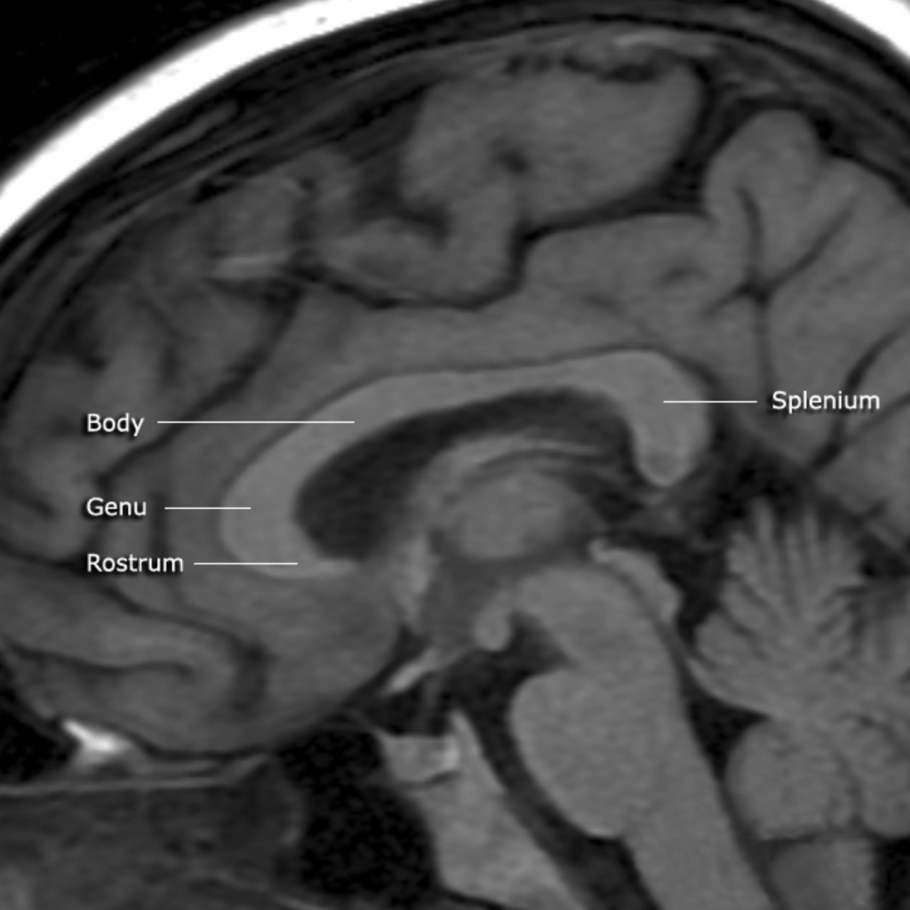

Каллозотомия мозолистого тела

Комиссуральные волокна головного мозга

Мозолистое тело человека